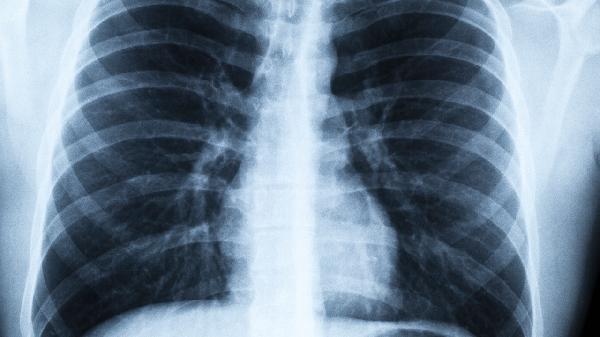

老张今年65岁,烟龄比很多年轻人的年龄还长。最近体检时,医生指着CT片上的阴影说:"这肺都快成煤球了!"其实像老张这样的老烟民不在少数,戒烟对他们来说就像要戒掉呼吸一样难。但你知道吗?戒烟后20分钟血压就开始下降,8小时后血氧就能恢复正常。